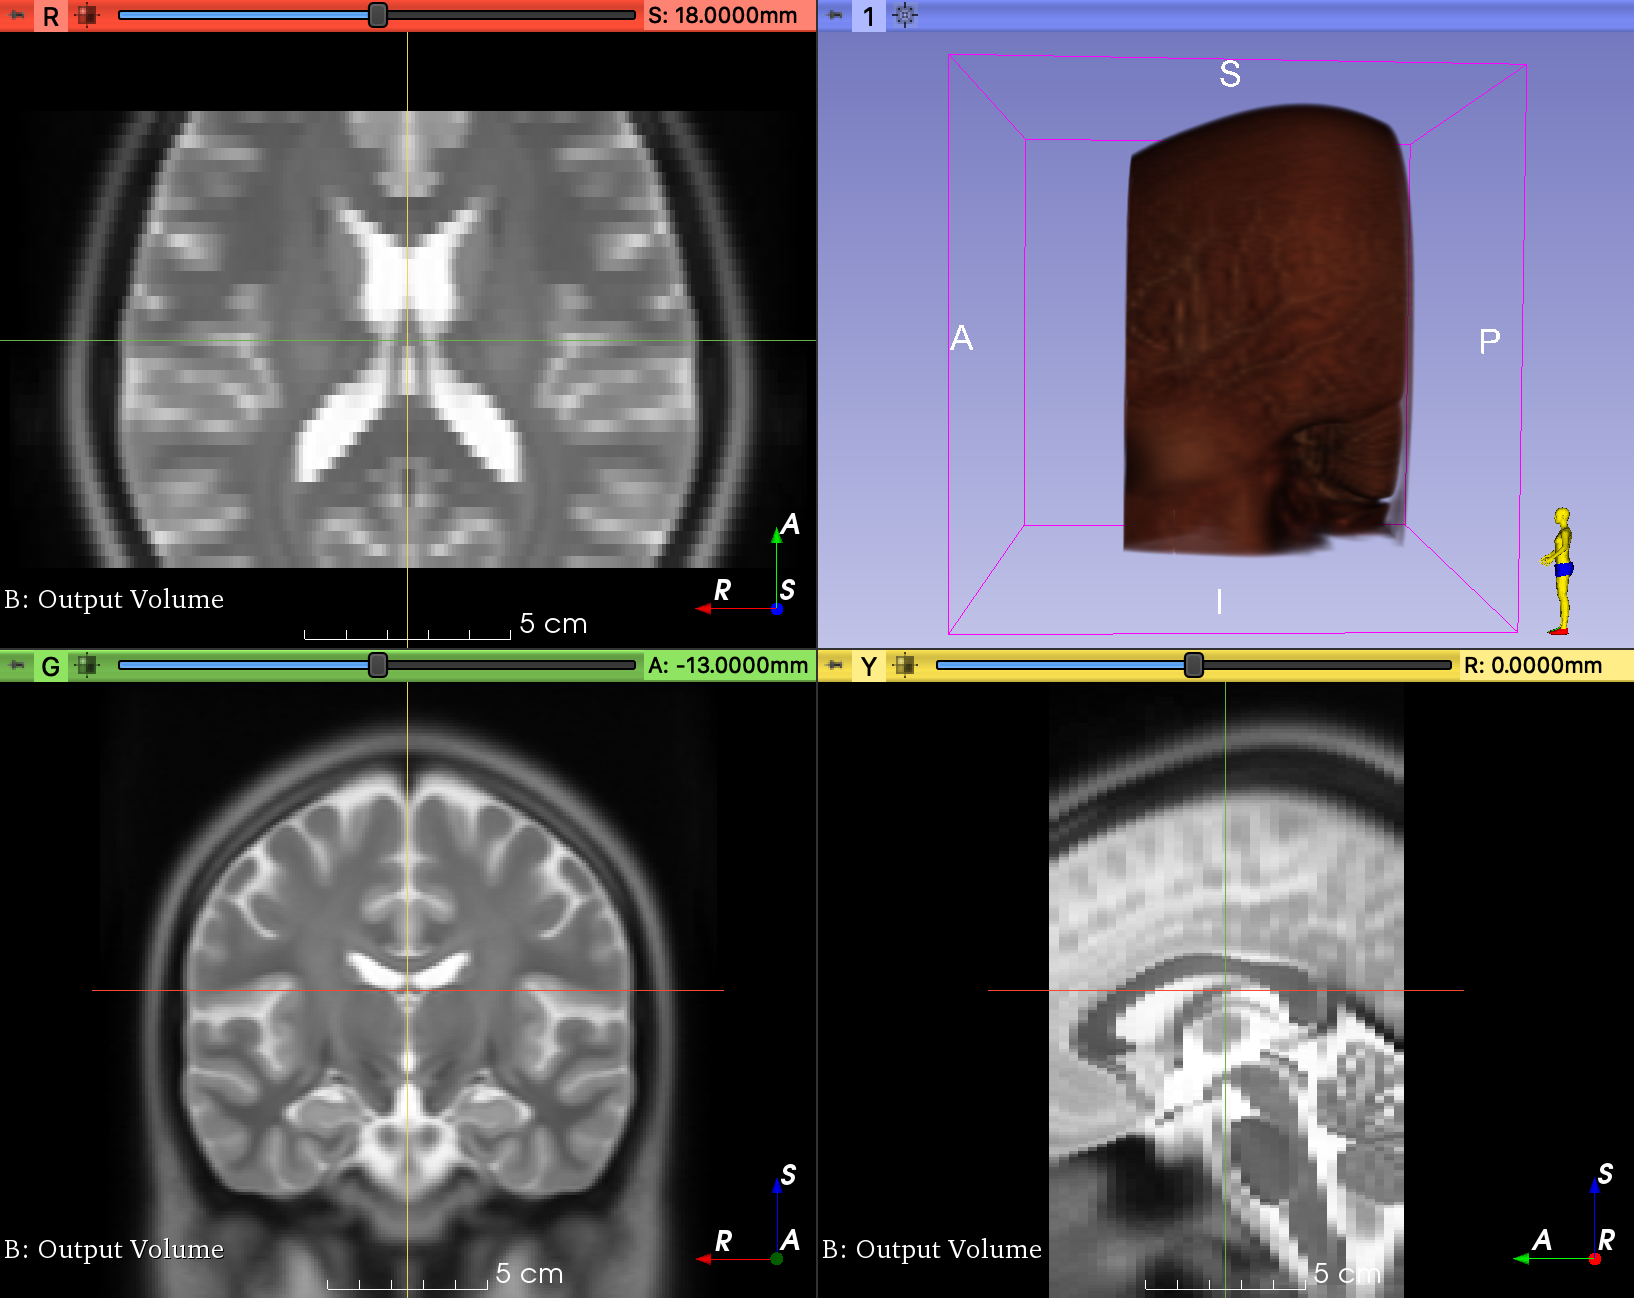

In multi- imaging sometimes the affine matrix may not be the same. Some of the example you have all images are preprocess, so I can see one could pre-process all images and then load like you indicated to concate in the channel. I am just experimenting as of now loading the images without having to do pre-processing in separate steps. Your package seems ideal to accomplish those tasks. Task: |

The docs for

Therefore, it should work if you do something like: subject_a = tio.Subject(image=tio.ScalarImage(["A.jpg", "B.img"])) |